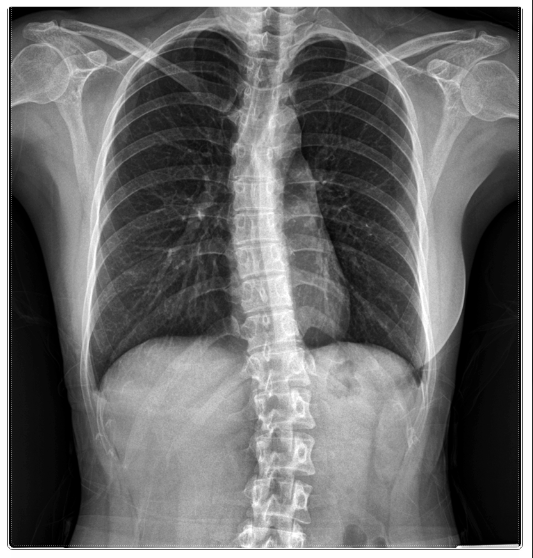

허리는 구조적으로 ‘S자 곡선’을 유지할 때 가장 안정적입니다.

이 곡선이 무너지면 디스크에 압력이 집중되어 다시 통증이 생기죠.